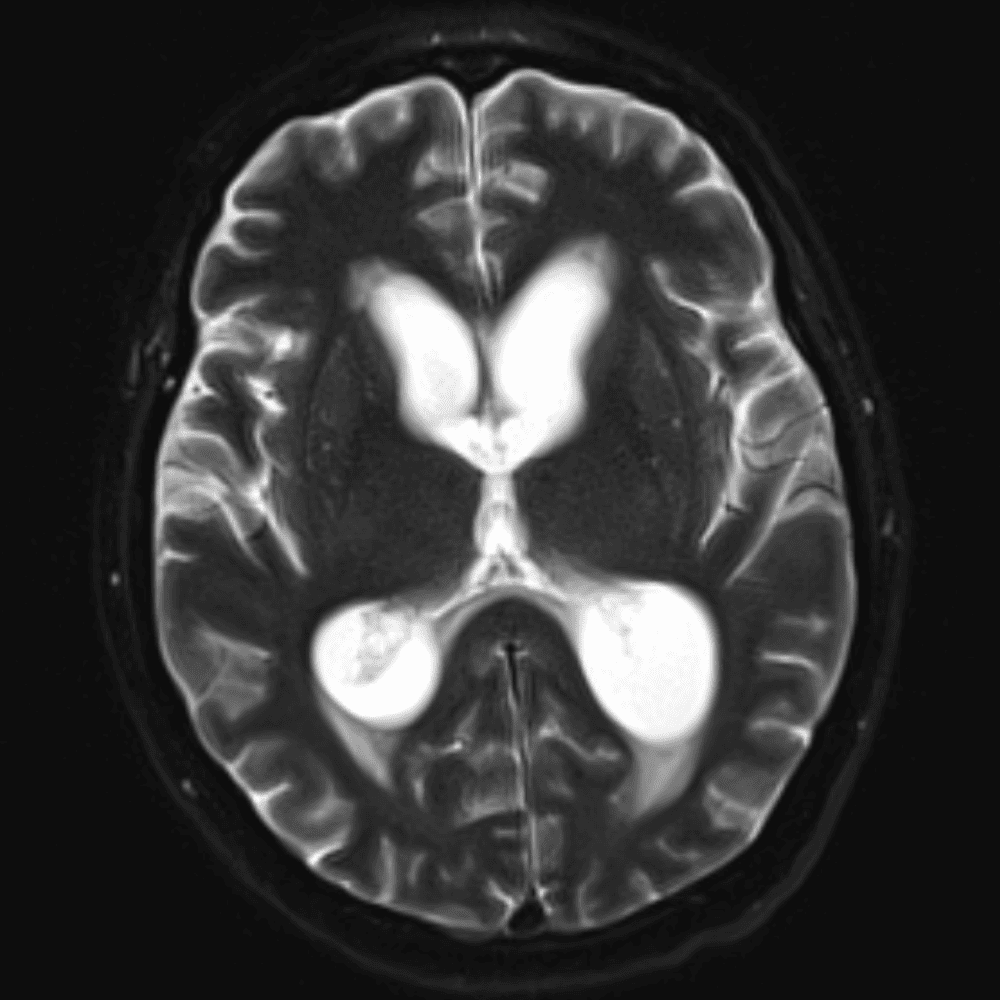

๋‹น์ง ์‹œ ํ”ํžˆ ๋ณผ ์ˆ˜ ์žˆ๋Š” ์‚ฌ๋ก€์˜ ์ „ํ˜•์ ์ธ ์˜ˆ๋ฅผ ํฌํ•จํ•ฉ๋‹ˆ๋‹ค.

39 ์‚ฌ๋ก€

์—ฐ์Šต

๋ฏธ๋ฌ˜ํ•˜๊ฑฐ๋‚˜ ์–ด๋ ค์šด ์‚ฌ๋ก€์™€ ์ผ๋ถ€ ์ •์ƒ ์‚ฌ๋ก€๋ฅผ ํฌํ•จํ•˜์—ฌ ๋‹น์ง์„ ์‹œ๋ฎฌ๋ ˆ์ด์…˜ํ•ฉ๋‹ˆ๋‹ค.

50 ์‚ฌ๋ก€